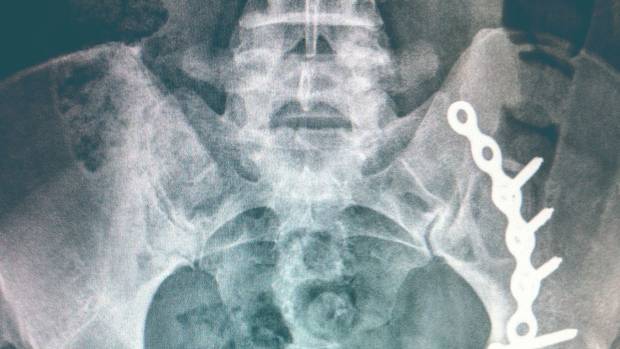

This MRI a year after his car accident shows damage to Terry Blais’s cervical spine, which deteriorated more as he fought his insurance company for benefits.

Mr. Blais suffered painful complications from a cervical spine injury that was discovered long after his vehicle was broadsided, giving him severe whiplash. He battled TD Insurance for six years after it stopped paying for treatment, such as physiotherapy, that the public system does not cover, and lost income.

Mr. Blais also found an odd mistake in his records. One report cited results from a lumbar spine MRI, saying it showed no abnormalities. Mr. Blais did not have an MRI on the date listed, or with that result, a fact his doctor's office later confirmed.

The MRI Mr. Blais did have on his cervical spine clearly showed his injuries. He now thinks the incorrect MRI in his report could have left the wrong impression.